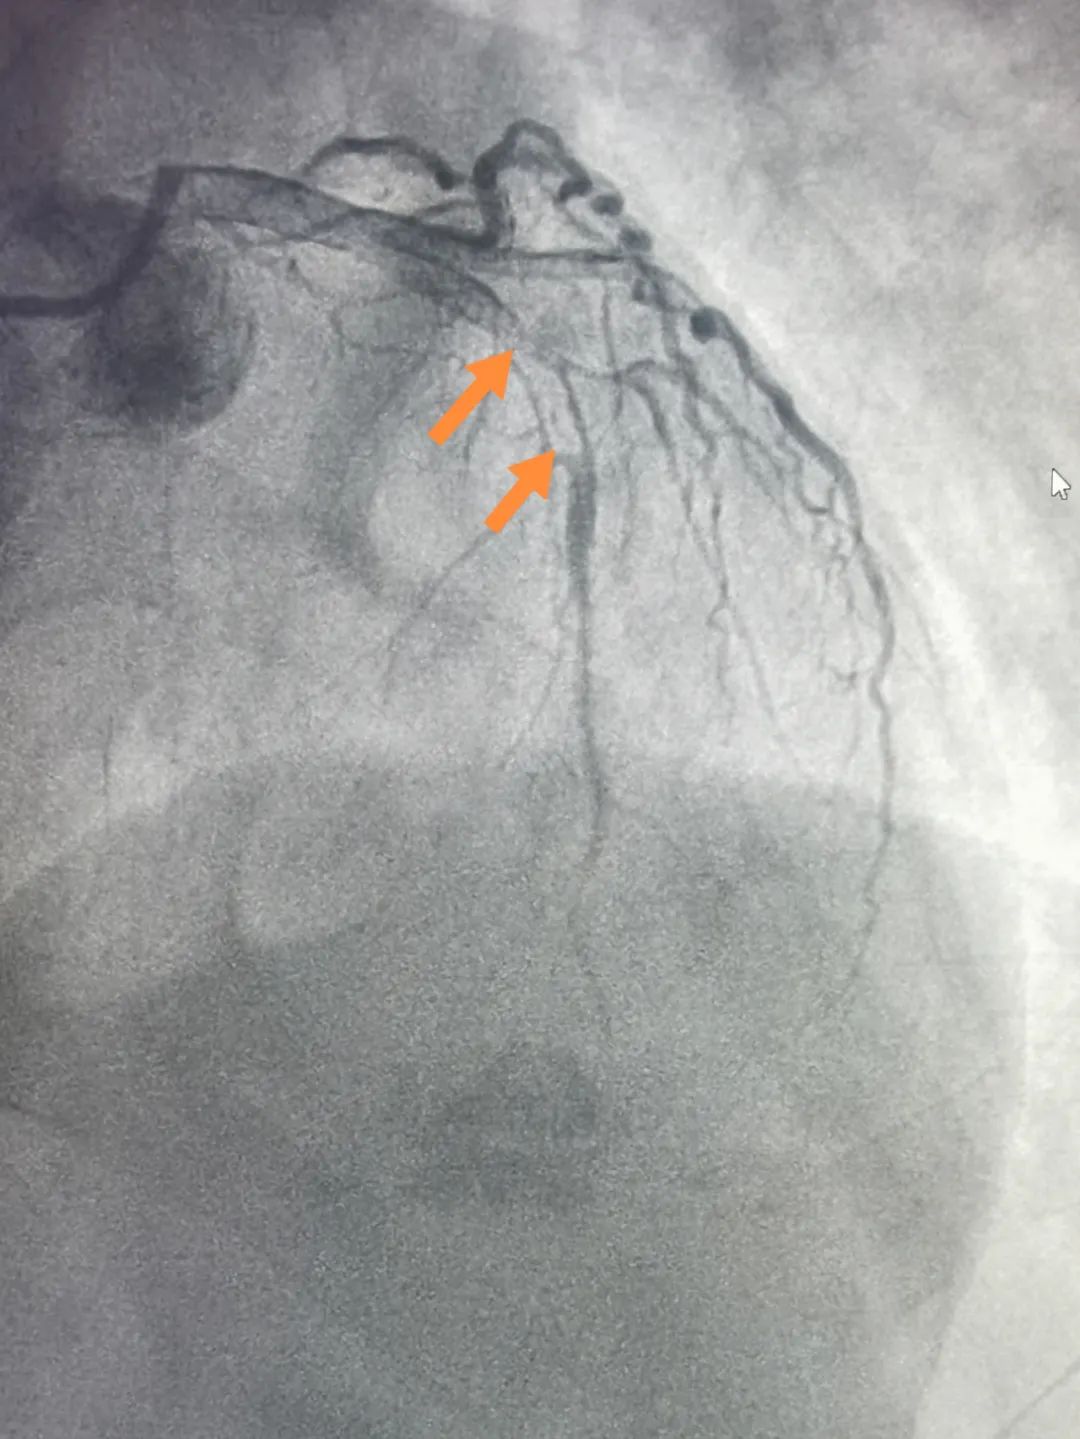

16:24在医生精确操作下导丝通过“罪犯血管”前降支;

17:17前降支植入支架1枚;手术成功完成,患者张大哥安返心血管内科重症CCU病房。